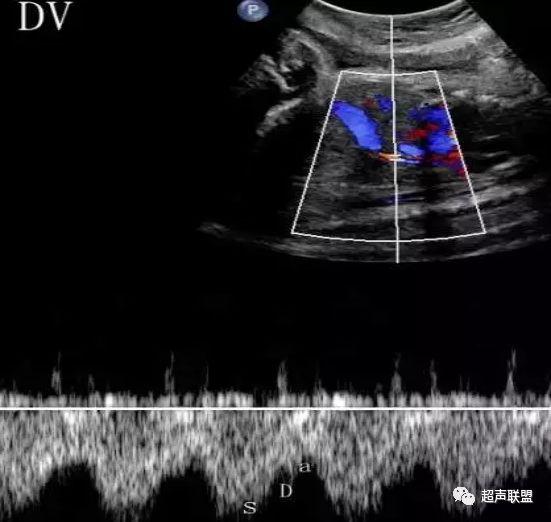

3 胎儿静脉导管

当右心负荷增大,心功能失代偿时,静脉回流受阻,静脉导管a波收缩期流速下降,血流消失甚至倒置。

5、静脉导管:a波消失或反向(见于严重的胎儿宫内缺氧);

7、宫内缺氧时肾动脉及腹主动脉的血流频谱为舒张末期血流的降低,RI及PI值会逐渐升高,若血流再分配严重时其舒张末期的血流将会消失甚至出现反向血流的产生。同时静脉导管也会反映缺氧时心脏功能的情况,当胎儿右心负荷增大,心脏功能失代偿时,静脉回流将会受阻,静脉导管心房收缩期流速逐渐下降,其血流消失甚至于血流倒置。

图5 胎儿宫内正常静脉导管

图6 胎儿宫内缺氧时静脉导管a波反向